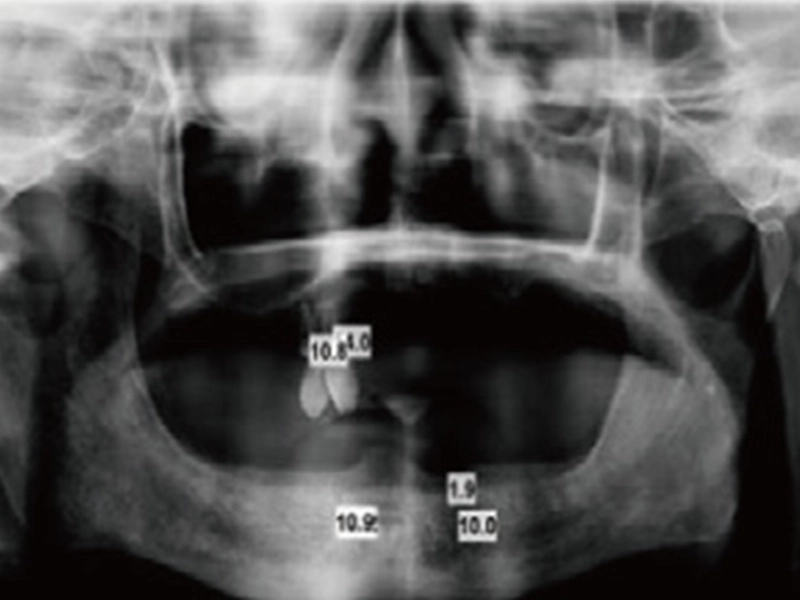

एक्स-रे लें

एक्स-रे लें और दंत प्रत्यारोपण के लिए प्लेसमेंट स्थान को परिभाषित करें।